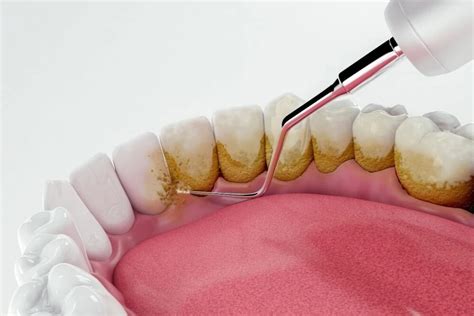

El sarro o cálculo dental tiene que ser eliminado en la clínica dental mediante una profilaxis dental profesional. Existen diferentes métodos para quitar el sarro:

- Ultrasonidos: El empleo de ultrasonidos es especialmente útil cuando el sarro está ubicado por encima de la línea de las encías (unión del diente con la encía). Logran desprender el cálculo en fragmentos sin dañar la superficie dentaria. Es muy importante que el proceso sea profusamente refrigerado con agua, pues los ultrasonidos producen un aumento térmico que podría causar dolor y daño en la estructura dentaria.

- Curetaje: Las curetas dentales son dispositivos manuales con formas muy variadas, de tal manera que consiguen adaptarse perfectamente a la superficie de los dientes. Permiten llegar bien a los espacios que hay en el surco de la encía. Allí se acumula el denominado sarro subgingival, especialmente nocivo para los tejidos gingivales al estar colonizado frecuentemente por patógenos periodontales muy dañinos. En el caso de que el sarro se haya acumulado bajo las encías, es necesario realizar un curetaje o raspado dental. Este implica una limpieza más profunda, que sí suele requerir la aplicación de anestesia local.